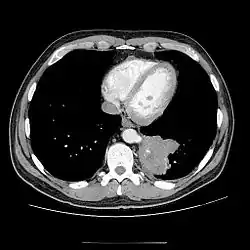

CT

- CT scans have 90% accuracy in the diagnosis of pulmonary sequestration.

- The most common appearance is a solid mass that may be homogeneous or heterogeneous, sometimes with cystic changes.

- Less frequent findings include a large cavitary lesion with an air-fluid level, a collection of many small cystic lesions containing air or fluid, or a well-defined cystic mass.

- Emphysematous changes at the margin of the lesion are characteristic and may not be visible on the chest radiograph.

- CT technique for optimal depiction of lesions by using state-of-the-art volumetric scanning requires a fast intravenous (IV) contrast injection rate and appropriate volume and delay based upon size.

- Multiplanar and 3D reconstructions are helpful.